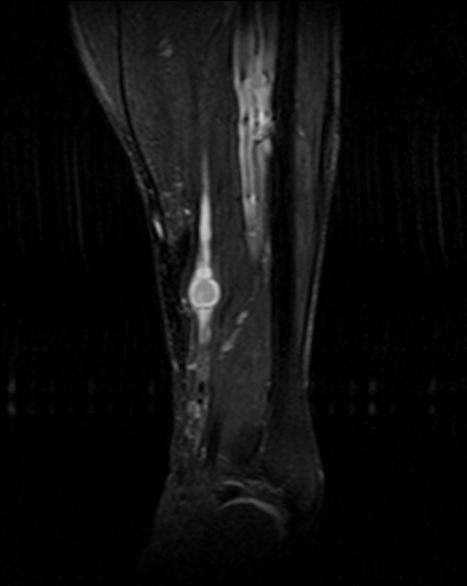

4.2 RM con contraste (prueba de elección)

- T1: señal baja–intermedia respecto a músculo.

- T2/STIR: señal alta, a menudo heterogénea (degeneración quística en schwannomas antiguos).

- Signos orientativos: relación con el nervio (fascículo entrante/saliente), “fascicular sign”, “split-fat sign” (en planos profundos). El “target sign” no es exclusivo.

- Contraste: realce de componente sólido; las áreas quísticas no realzan.

- Neurografía RM: útil si el nervio de origen no es evidente o para planificar cirugía preservadora.

4.3 Imágenes

Schwannoma de partes blandas

Cortesía: Dr. Arturo Mahiques